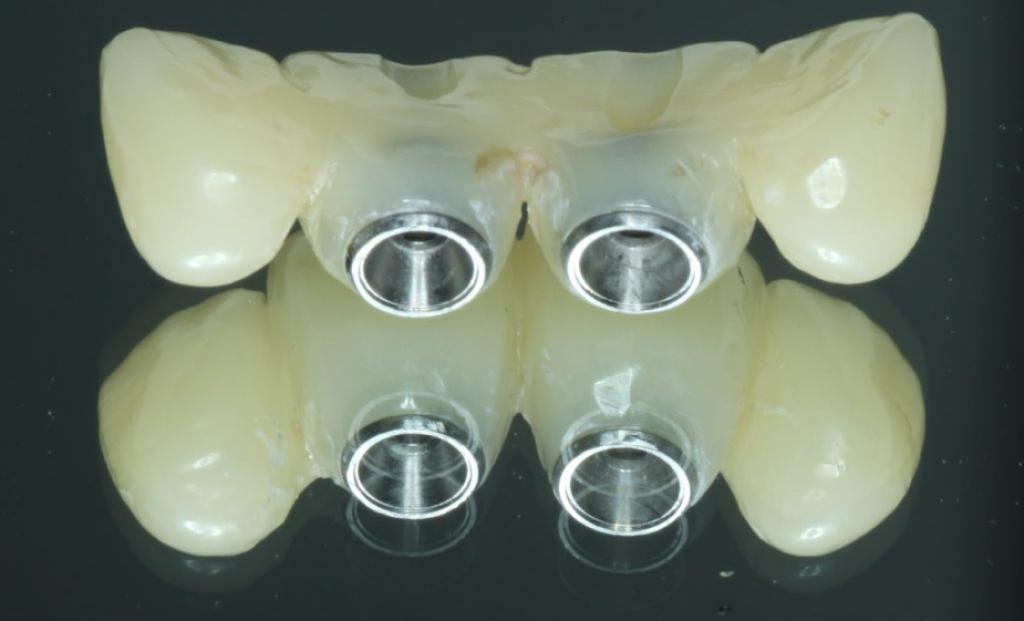

При множественной имплантации рекомендуется выбирать абатменты со следующи ми свойствами:

- Легкий доступ к абатменту, простота ортопедического протокола

- Винтовая или гибритдная цементно-винтовая фиксация

- Исправление проблем соосности при помощи угловых абатментов

Абатменты должны быть выбраны до того, как будут сделаны оттиски или внутриротовое сканирование для изготовления окончательного протеза. Соединять абатменты на слепке, сделанном с уровня имплантата и только потом изготавливать протез неправильно. Большинство систем имплантатов имеют абатменты, разработанные с учетом вышеперечисленных преимуществ, в основном известные как абатменты с несколькими базами, абатменты с несколькими единицами, трансформируемые абатменты, абатменты с винтовой фиксацией, конические абатменты, универсальные абатменты и другие.